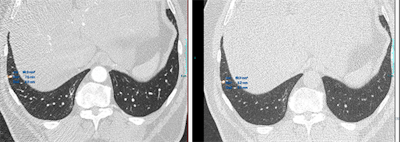

Factors affecting 3D volumetry consist of those related to the nodule, including its dimensions, location, morphology, and density (solid/ground glass). Various technical parameters are important, particularly slice thickness, software and segmentation algorithms, and inspiratory/expiratory factors. Also relevant here are operator-dependent factors plus interscan, intrascan, and hemodynamic (e.g., cardiac cycle) factors.

"Studies using a 'coffee-break' model showed that different factors such as positioning, inspiratory effort, heart rate, and hemodynamic changes all contributed to interscan variability of nodule's volumetric measurements," the authors stated, adding that inter- and intraoperator variability of less than 1% and interscan variability of 20% can occur. Volume measurement in small nodules can be more than 30% during the cardiac cycle.

The estimated volume of a nodule is based on the number of voxels in the segmented region, while the percentage of voxels with partial volume artifact decreases as the nodules' dimensions increase and the slice thickness decreases. Smaller nodules have a greater percentage of voxels that are affected by partial volume artifact, and volumetric analysis is dependent on the size of the nodule. Furthermore, adjacent location to the airways, vessels, and pleura limits the margin's definition and subsequent segmentation of the nodule.